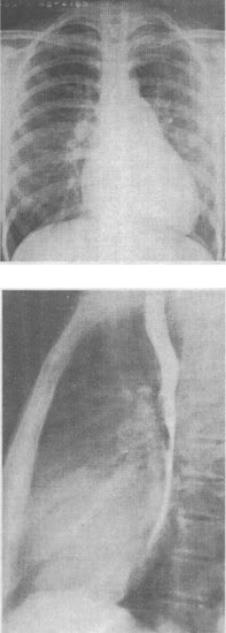

患儿,4岁,活动后心悸、乏力,胸骨左缘可闻及杂音,扪及震撼,胸部正侧位摄片如图,最可能的诊断是()。

A、房间隔缺损

B、室间隔缺损

C、动脉导管未闭

D、肺动脉狭窄

E、法洛四联症

B